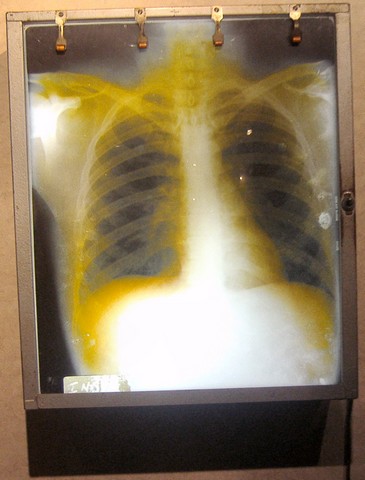

Photograph by Cybrary Man